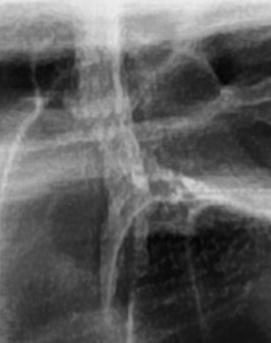

가장 주의해야 하는 문제 중에 치주염이 진행되면 어금니 뒤쪽뿐만 아니라 전체적인 잇몸이 약해질 수 있어요. 치주염은 치아를 둘러싸고 있는 조직이 손상되는 질환인데 특히 잇몸이 자주 붓거나 피가 나는 경우에는 치주염이 진행되고 있는 신호일 수 있기 때문에 단순한 잇몸 붓기로 넘기지 않는 것이 좋으며 치료를 받지 않으면 결국 치아를 지탱하는 뼈가 약해지고, 심한 경우에는 치아가 흔들리거나 빠질 수도 있었어요.

결론적으로는 통증이 심하거나 염증이 오래 지속되는 경우에는 치과를 방문해서 정확한 진단을 받는 것이 중요한데 단순한 잇몸 염증이라면 치석 제거와 항생제 치료로 호전될 수 있지만, 치주염이 진행된 경우라면 보다 적극적인 치료가 필요할 수 있어요. 만약 사랑니로 인해 잇몸이 자꾸 붓는다면 사랑니 발치를 고려해야 하겠고 사랑니가 완전히 매복되어 있다면 수술적인 방법으로 제거해야 할 수도 있어요. 특히 반복적으로 붓는다면 사랑니 검사를 받아보거나, 치과에서 정밀 검진을 통해 치주 상태를 확인하는 것이 필요하다는 점에서 어금니 근처의 잇몸이 반복적으로 불편하다면 꼭 치과를 찾아보시길 바라고 있어요